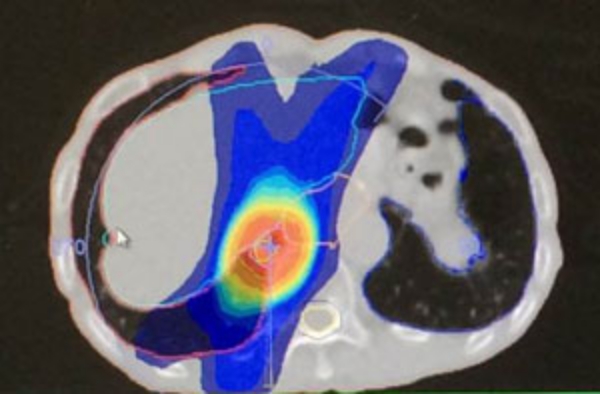

小肺がんの照射

肺がん+リンパ節

はじめのうちは、広く照射。その後、縮小照射正常肺にできるだけ当たらないように3個に分けて照射